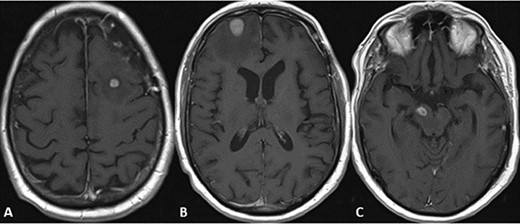

CASE

Spindle cell neoplasm with pleomorphic epithelioid features, multinucleation, mitoses and necrosis, involving pulmonary artery (A, B) and brain (C, D), H&E.